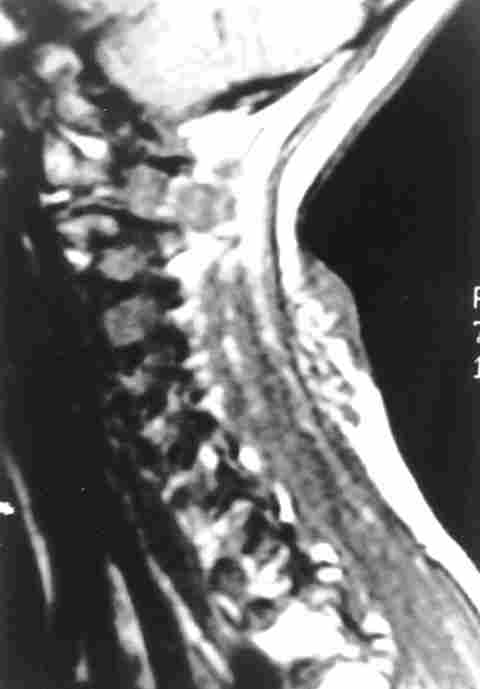

RMN DE NEUROFIBROMA PLEXIFORME EN REGIÓN CERVICAL.